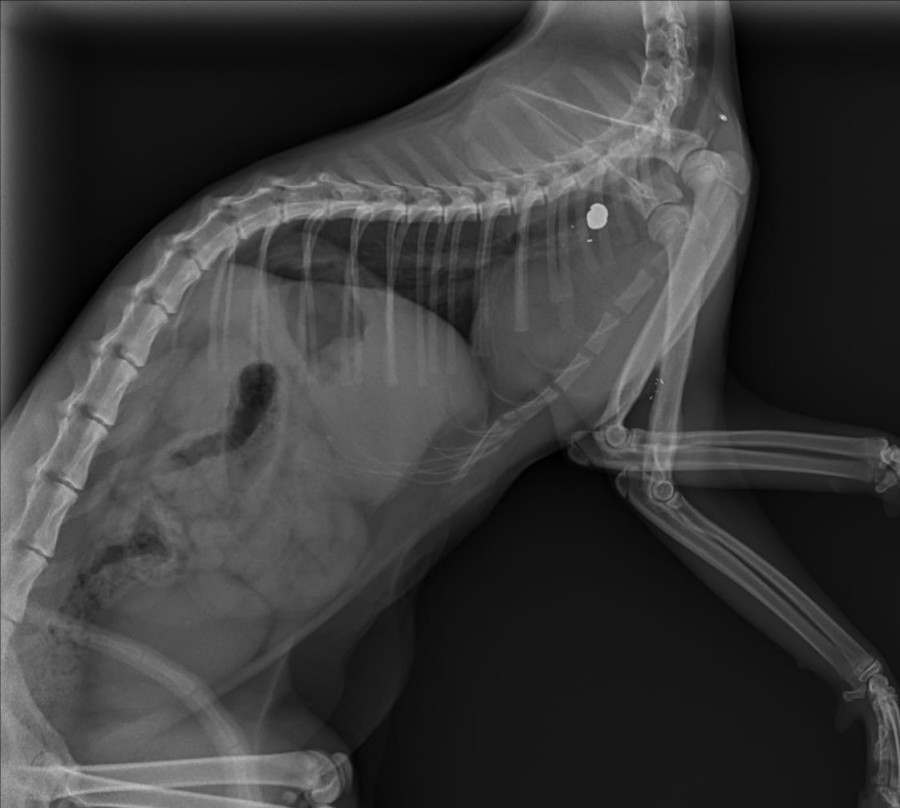

Wir sind von vielen verschiedenen Optionen ausgegangen…vertreten, versprungen, evtl. ein Infekt mit Fieber…aber was uns dann vom Tierarzt auf dem Röntgenbild gezeigt wurde, hat uns sprachlos gemacht.

In der linken Schulter des kleinen zarten Katzenmädchens befindet sich ein Projektil, vermutlich von einem Luftgewehr.

Irgendwann muss irgendwer auf dieses kleine unschuldige Wesen geschossen haben als sie noch sehr klein war, da es äußerlich keine Wunde mehr gab.

Leider ließ sich das Projektil nicht entfernen, die Gefahr Muskeln und Sehnen auf Dauer zu schädigen um bis zum Projektil vorzudringen wäre einfach zu groß gewesen.